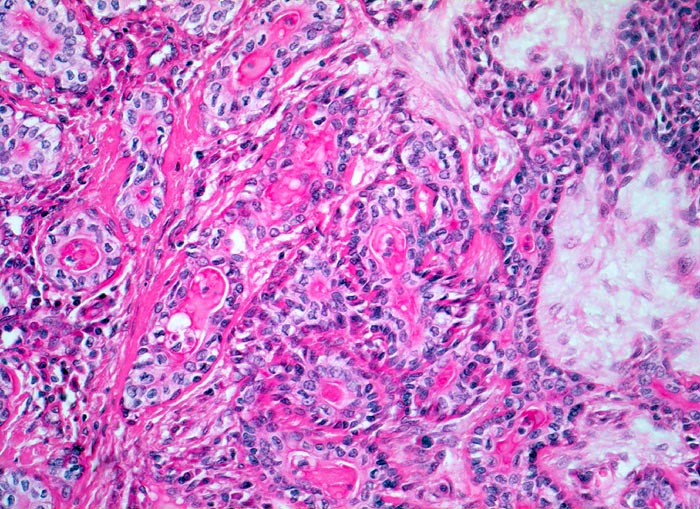

PathoPic – image database / PathoPic ID 3422 - Pleomorphes Adenom der Speicheldrüse

Pleomorphes Adenom der Speicheldrüse

benigner Tumor

Parotis

Epitheliale Gangstrukturen ausgekleidet lumenwärts von einem einschichtigen kubischen Epithel und einer äusseren Myoepithelschicht. Die Myoepithelien bilden stellenweise solide $o{qy8062494Myoepithelien} Zellmassen. Wenig mukoides Stroma. Die Drüsen sind ausgekleidet von kubischem Epithel und enthalten homogene hyaline Massen.

5cm grosser bekapselter Tumor in der linken Parotis.

Schmerzlose Vergrösserung der Parotis.

Histologie

200